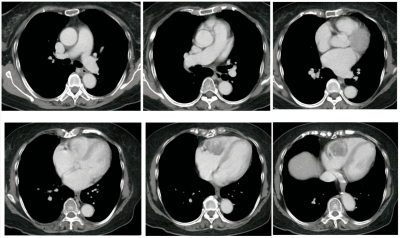

縦隔条件の胸部造影CTを別に示す。

異常所見を示す心臓の部位はどこか。

d. 右心室

右心室に腫瘤を認める。